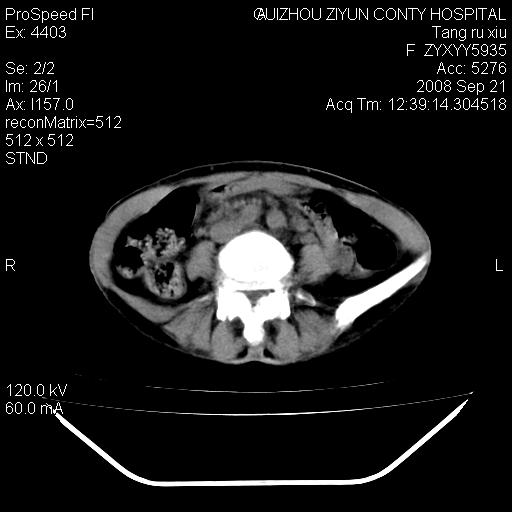

f、57岁,上腹痛.2月,近来胸闷。2月前在外院摄胸片示左侧胸腔少量积液。

(患者腹痛入院,欲吐,临床医生说禁饮,所以没有口服对比剂)

肝脏大小形态尚可,其实质内可见多发大小不等的低密度影,边缘模糊。肝门区结构紊乱,腔静脉腹主动脉旁可见多发软组织密度影,部分融合成团块状,并向下延伸。胰腺及十二指肠结构显示不清。腹腔内脐后肠管走形僵硬,管壁可见增厚。盆腔内可见多个淋巴结影。所扫层面左侧胸腔可见大量弧形水样密度影,其内侧可见被压缩的肺组织影。左侧胸壁可见一小结节样软组织密度影,边缘模糊。心脏纵隔向右侧移位。心脏包膜内可见囊样低密度影,其内侧心房室周围可见一圈气体样密度影。纵隔内大血管旁可见多发软组织团块影,部分融合。

1.腹膜后淋巴瘤侵及肝脏,肺内及纵隔内多发转移。2.左侧大量胸腔积液并压缩性肺不张。3.心包脓肿可能,转移不除外。4.脐后局部肠管管壁增厚,考虑炎症可能,肿瘤不除外。